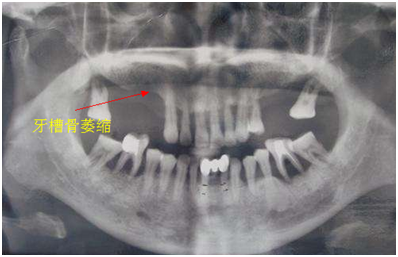

6、牙槽骨萎缩

牙齿缺失后正常咬颌力对牙槽骨的生理性刺激不复存在,牙槽骨均会出现不同程度的废用性萎缩,并且会给后期假牙修复及维持口腔颌面部的平衡和稳定带来巨大的困难。